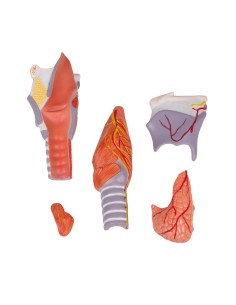

3B Scientific, modello anatomico funzionale di laringe: W42503